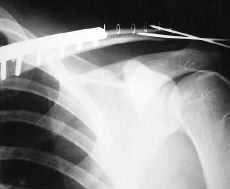

Paciente varón de 29 años de edad, sin antecedentes de interés, que sufre caída accidental con traumatismo directo sobre hombro izquierdo, presentando dolor e impotencia funcional en dicha articulación. A la exploración física se objetivó dolor y deformidad en hombro izquierdo con signo de la tecla positivo, sin déficit vasculonerviosos distales. En las radiografías realizadas (Fig. 1) se apreció una fractura de tercio medio de clavícula izquierda desplazada, asociada a luxación acromioclavicular tipo II de la clasificación de Tossy y cols.6,7 Fue intervenido quirúrgicamente, realizando reducción y fijación de la fractura de clavícula izquierda con placa DCP, así como revisión de los ligamentos acromioclaviculares, en los que se comprobó su integridad y fijación de la articulación acromioclavicular con dos agujas de Kirschner (Fig. 2). El paciente fue inmovilizado con sling, cursando el postoperatorio sin ningún incidente; las agujas se retiraron a las 4 semanas (Fig. 3) y tras un período de 3 años de seguimiento se observó una movilidad completa e indolora, alcanzando arcos articulares en el hombro afectado comparables al lado sano, así como unos resultados funcionales en los que se alcanzó una puntuación máxima en la escala de Constant2,25,20 (25/30) (Figs. 4 y 5).

Figura 1. Rx preoperatoria en la que se aprecia ensanchamiento de la articulación acromioclavicular.